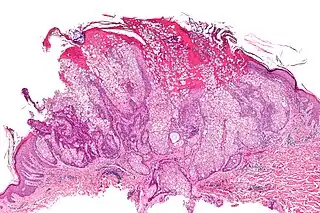

Adenoma sebáceo

Un adenoma sebáceo, es un tipo de adenoma, enfermedad cutánea que consiste en un tumor de crecimiento lento, habitualmente una pápula o nódulo de color rosa, carne o amarillo.[1]: 662 [2]

Los adenomas sebáceos aislados no revisten gravedad; sin embargo pueden estar asociados con el síndrome de Muir-Torre, una enfermedad genética que predispone al cáncer.[3]

Puede estar asociada con la esclerosis tuberosa. El término «adenoma sebáceo» es en realidad una denominación errónea.